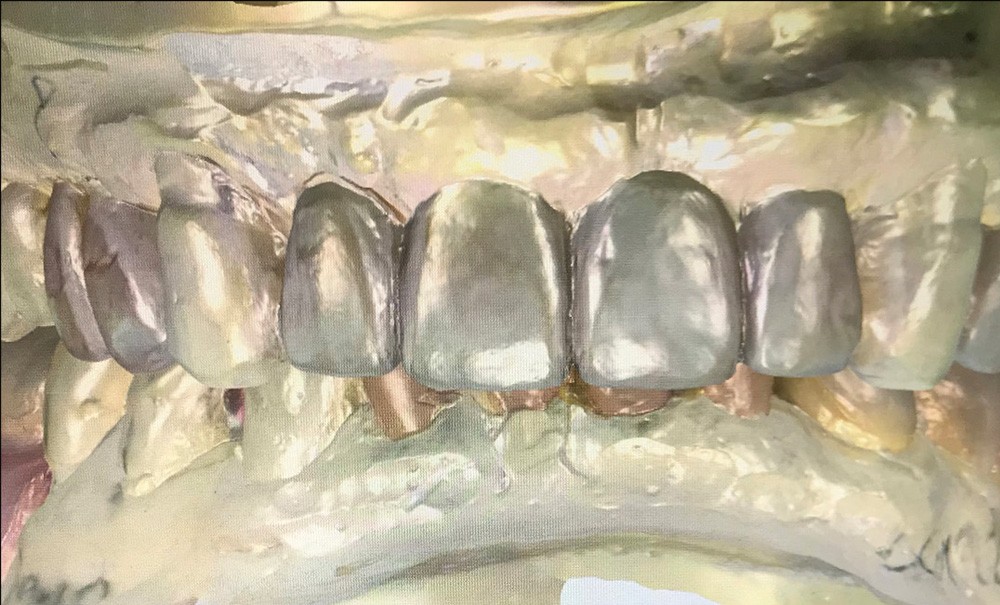

Reconstruction complexe : optimisation de la phase transitoire par CFAO

La conception et fabrication assistées par ordinateur s’invitent de plus en plus dans notre exercice quotidien. En effet, l’évolution considérable de ces dernières années en matière d’odontologie numérique permet une approche de plus en plus qualitative et ergonomique [1-4].

Cette technique autorise trois approches : la CFAO directe, la CFAO semi-directe et la CFAO indirecte [5].

Pour la CFAO directe, le praticien numérise les arcades au fauteuil, puis conçoit et fabrique la pièce prothétique au sein même du cabinet, à l’aide d’une machine-outil. La restauration peut alors être effectuée très rapidement, parfois même dans la séance, ce qui représente un avantage considérable [6].

L’atout majeur de la CFAO directe réside dans son extrême rapidité de mise en œuvre, associée à une grande précision d’exécution et l’élimination des risques d’erreurs dus à la dépendance des matériaux (tirage, décollement de matériaux, déformation de la zone de contact proximal, difficultés d’accès aux limites…). Avec l’empreinte numérique, le praticien gagne en précision [7,8].